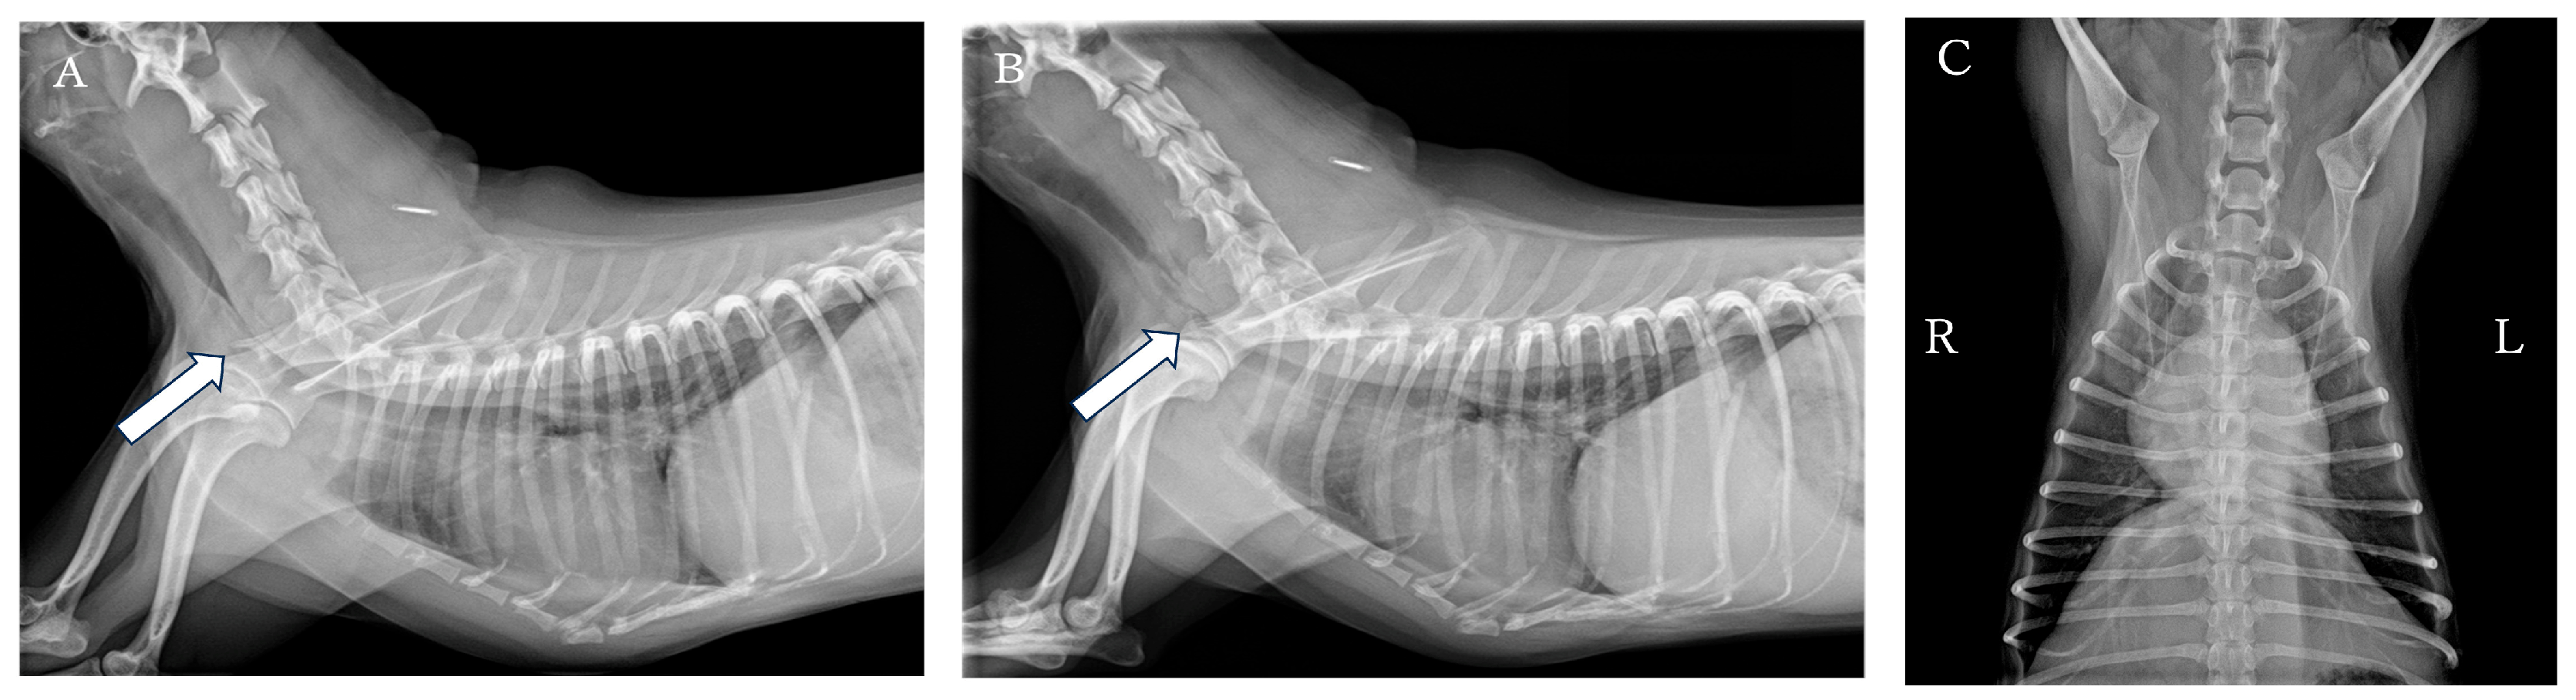

By approximately day 4 after starting medication, the respiratory status stabilized, and inspiratory effort decreased to about once per day. At the 4-week postoperative follow-up, nebulizer stimulation at home induced excitement, so nebulizer therapy was discontinued (Figure 6).

Figure 6. Cervicothoracic radiographic view of the dog obtained during postoperative follow-up after PLLP placement. (A) Right lateral view. (B) Ventrodorsal view. No stent deformation or tracheal narrowing at the fracture site or cranial to the stent was observed.